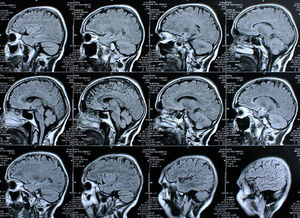

Gehirne: Affen und Menschen sind ähnlich (Foto: pixelio.de, Rike) |

Die Wissenschaftler scannten die Gehirne von 36 Menschen. Mit Hilfe eines Algorithmus erstellten sie eine bildliche Darstellung eines Bereiches des Gehirns, der mit der Theorie des Geistes in Verbindung gebracht wird, und brachten diese mit Bildern von Bereichen in Zusammenhang, die mit Fähigkeiten wie Gesichtserkennung und -interpretation verbunden sind.

In einem nächsten Schritt scannten die Forscher die Gehirne von zwölf Makaken in Hinblick auf ein ähnliches Muster. Ein Bereich der Gesichtserkennung verfügte über ein ähnliches Muster. Das legt den Schluss nahe, dass eine Fähigkeit zu abstraktem Denken vorliegen könnte. Laut Mars bedeutet das nicht unbedingt, dass diese Strukturen über die gleichen Funktionen verfügen.